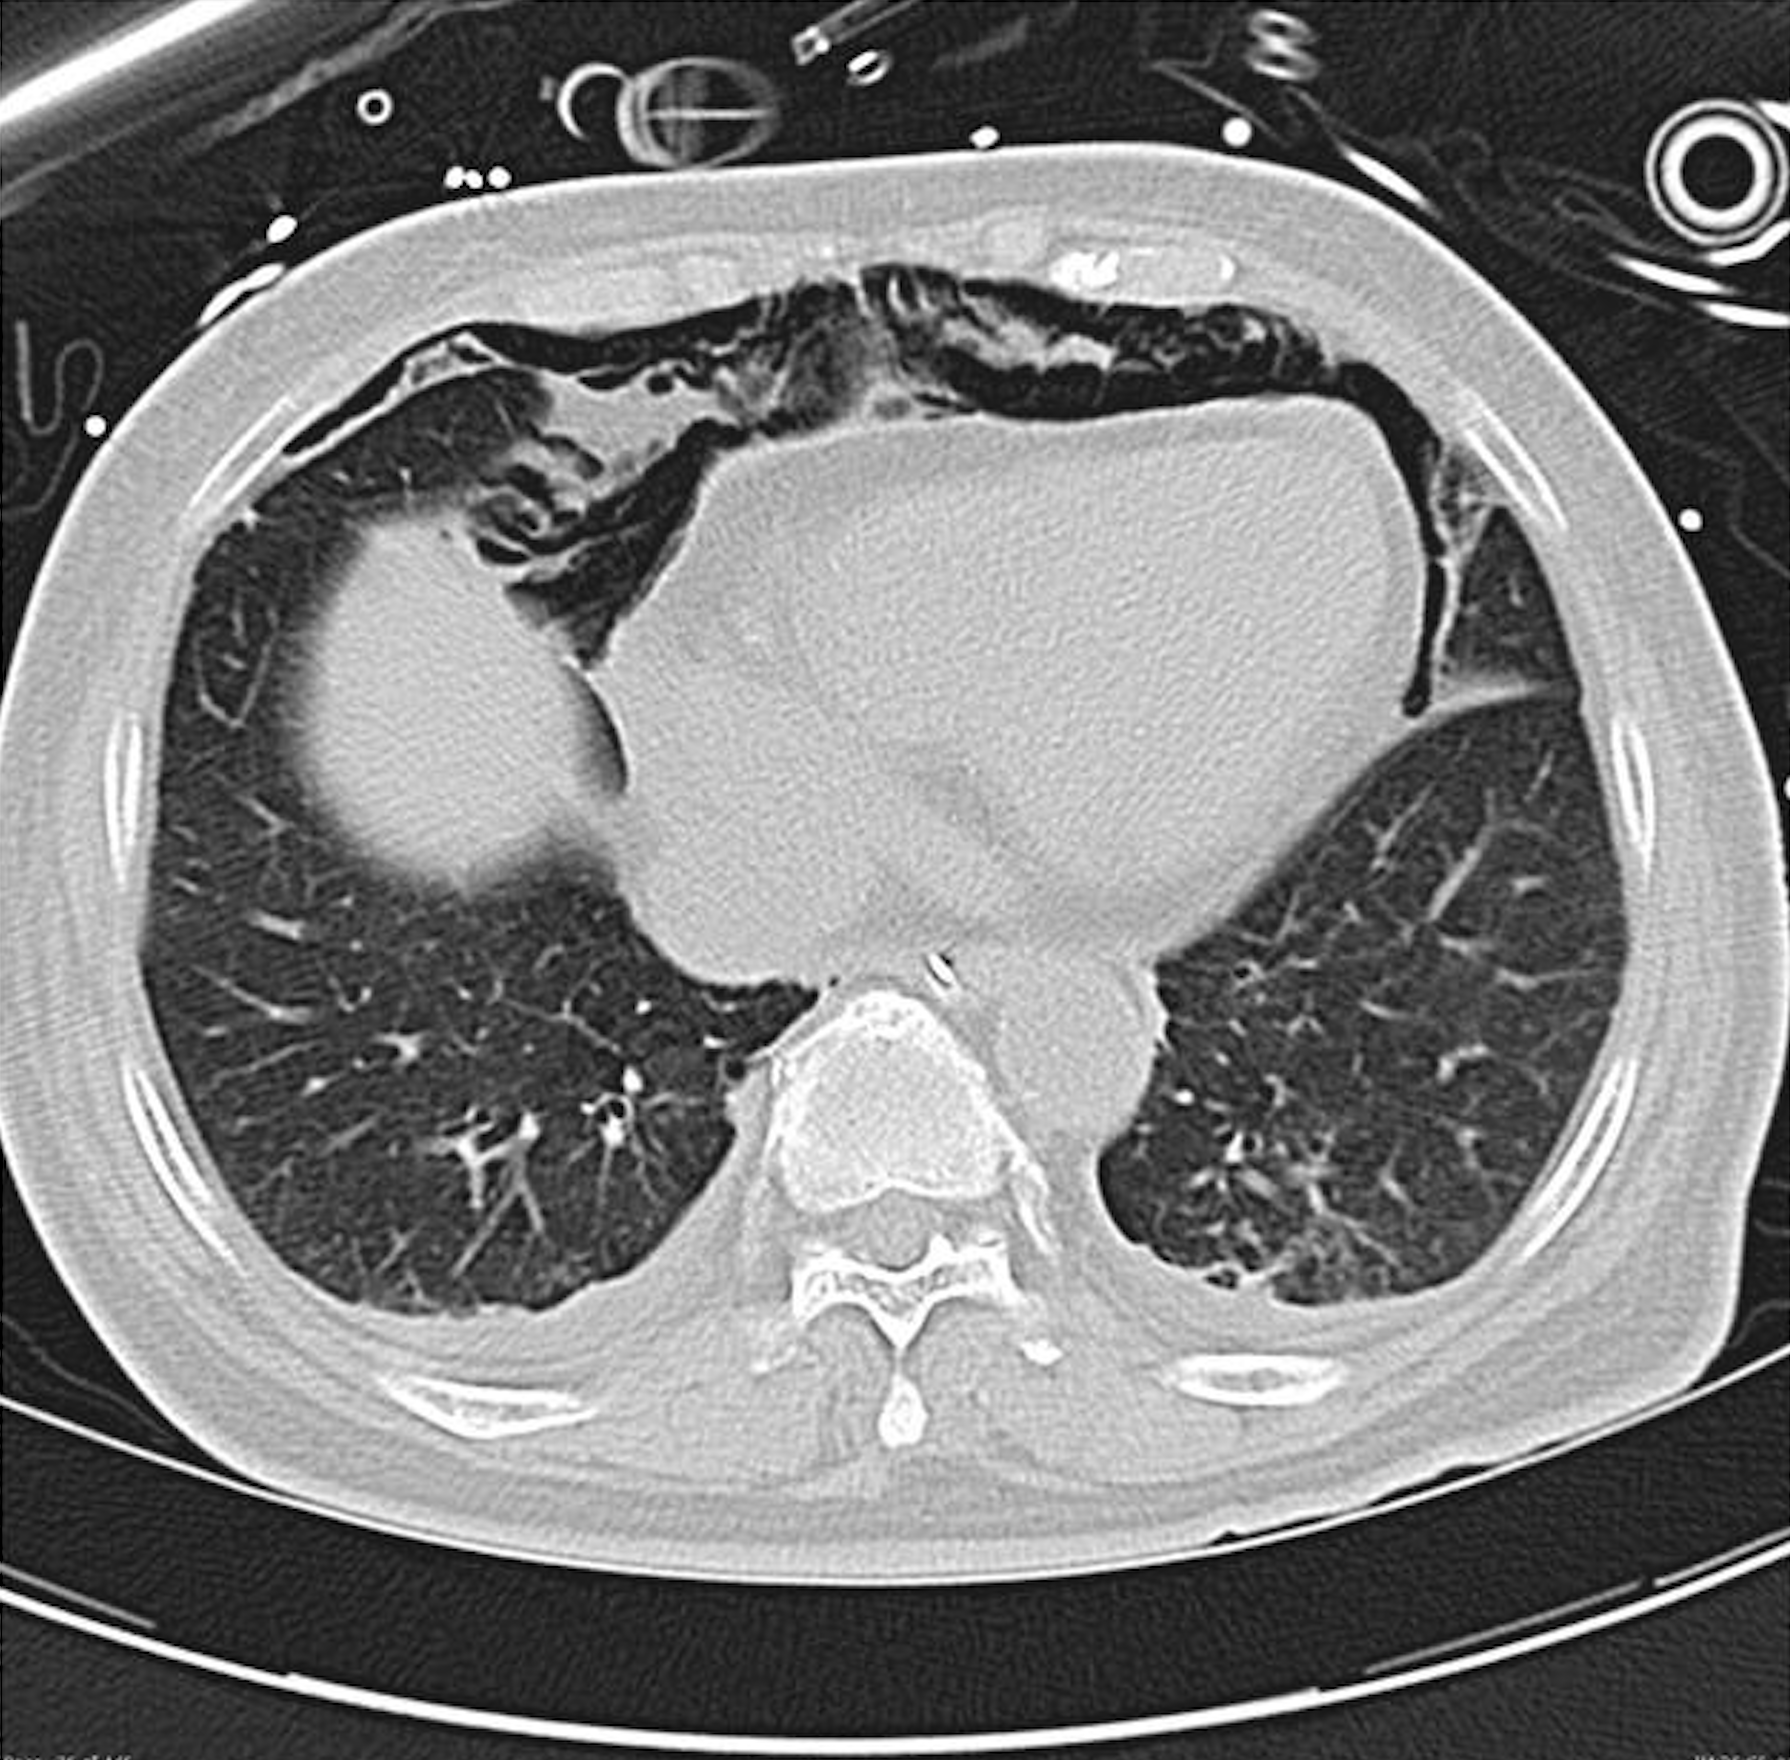

Aspect de rayon de miel

Définition : l’aspect en rayon de miel, également connu sous le terme anglais “honeycombing”, se caractérise par la présence de multiples petites cavités kystiques, organisées en plusieurs couches, séparées par des parois épaissies. On peut également observer un motif en forme de nid-d’abeilles. Cet aspect est identifiable sur les images obtenues par scanner thoracique en fenêtre […]